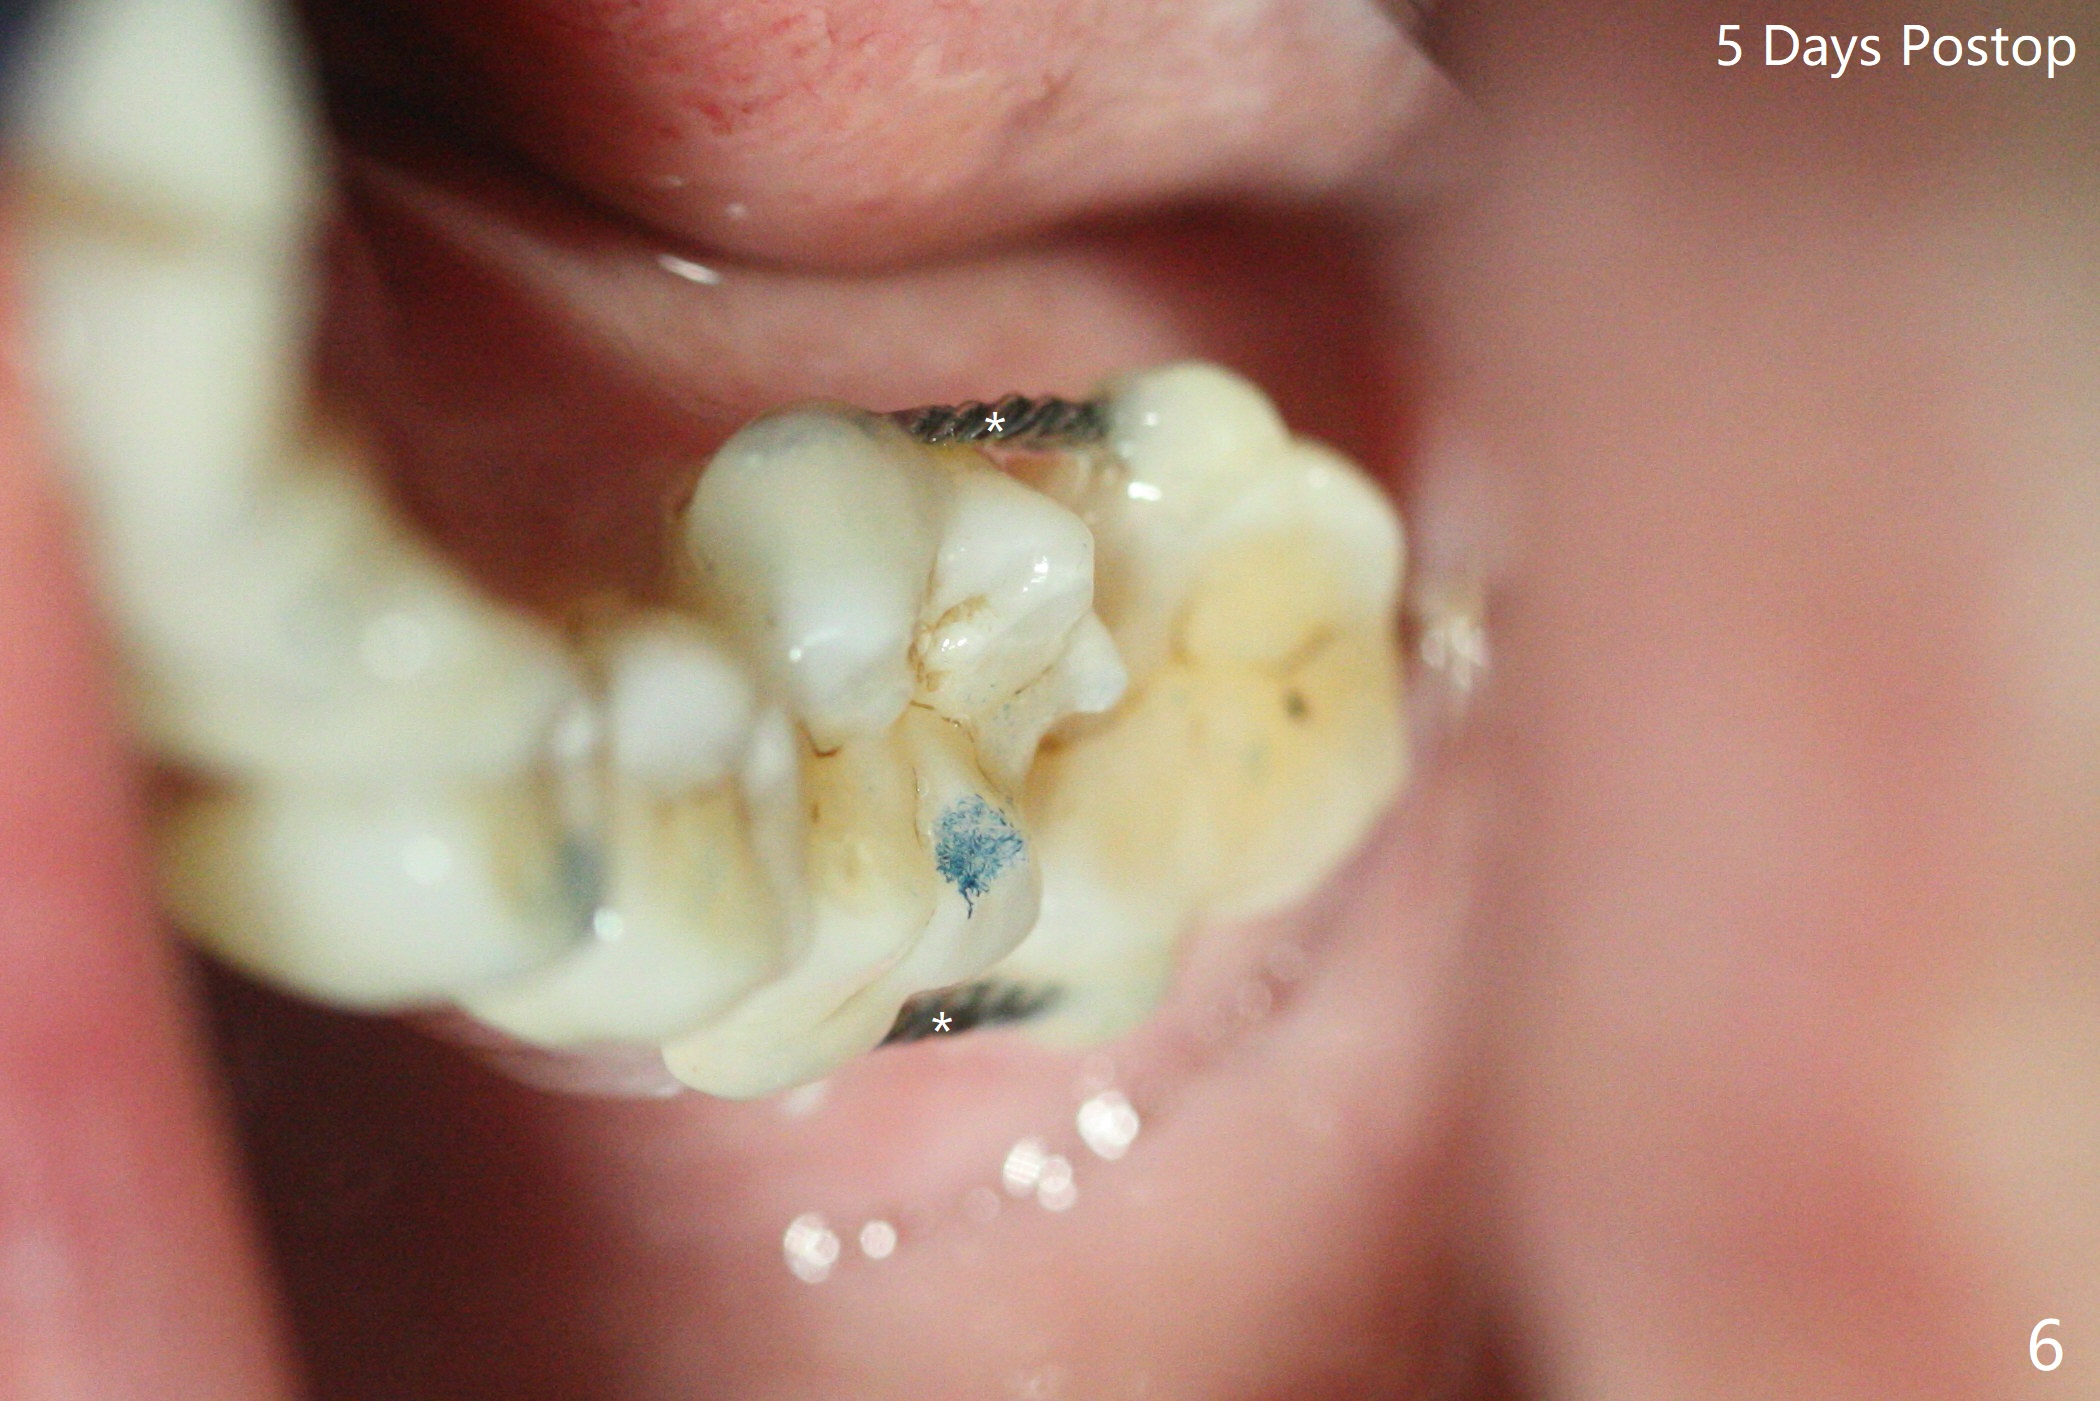

65岁女,南方人(广州),主诉左下肿胀,8舌侧粘膜穿孔(图一(舌侧观):<),初步问诊,回答:“全身没问题”,详细问诊:骨质疏松,静脉注射Reclast两年,准备拔除使用PRF修复缺损,全景片显示7远中骨质吸收严重(图二),因此8拔出后,牙槽窝塞入胶原塞(图五:C),将粘性骨粉放置7近中,远中(图五:白*)以及颊侧(黑*),把一片PRF膜覆盖骨粉(7颊侧,8牙槽窝口),另外一片放置于8舌侧穿孔(图四:箭头)颊侧,促进愈合,然后使用4-0 PGA缝合(图三(颊侧观),图四(舌侧观))。术后5天用钢丝(图六:*)和树脂固定松动牙,并且降低咬合。舌侧穿孔正在愈合(图七:>)。虽然术后三周智齿伤口裂开,但是没有症状,病人满意第二磨牙不再松动(图八),开始深洗。下次复诊拍摄根尖片观察骨质愈合。术后二个月第二磨牙远中没有骨质再生(图九),临床上远中牙根暴露。